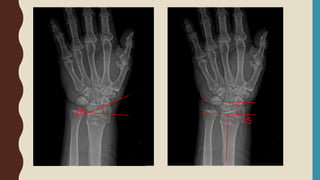

• 3 view of the wrist including true PA(PA zero), Lateral +/- Oblique

• Oblique view – useful for assess radial comminution, depression of radial styloid

RADIOGRAPHIC FINDINGD

• Extra or intra-articular fracture

• Dorsal angulation

• Dorsal tilt

• Dorsal comminution

• Radial shortening

• Ulnar styloid fracture

• ( Ulnar variance )

Unacceptable alignment

• Radial inclination < 15o

• Shortening > 5 mm

• Dosal tilt > 10o

• Volar tilt > 20o

• Articular step off or gap > 2 mm